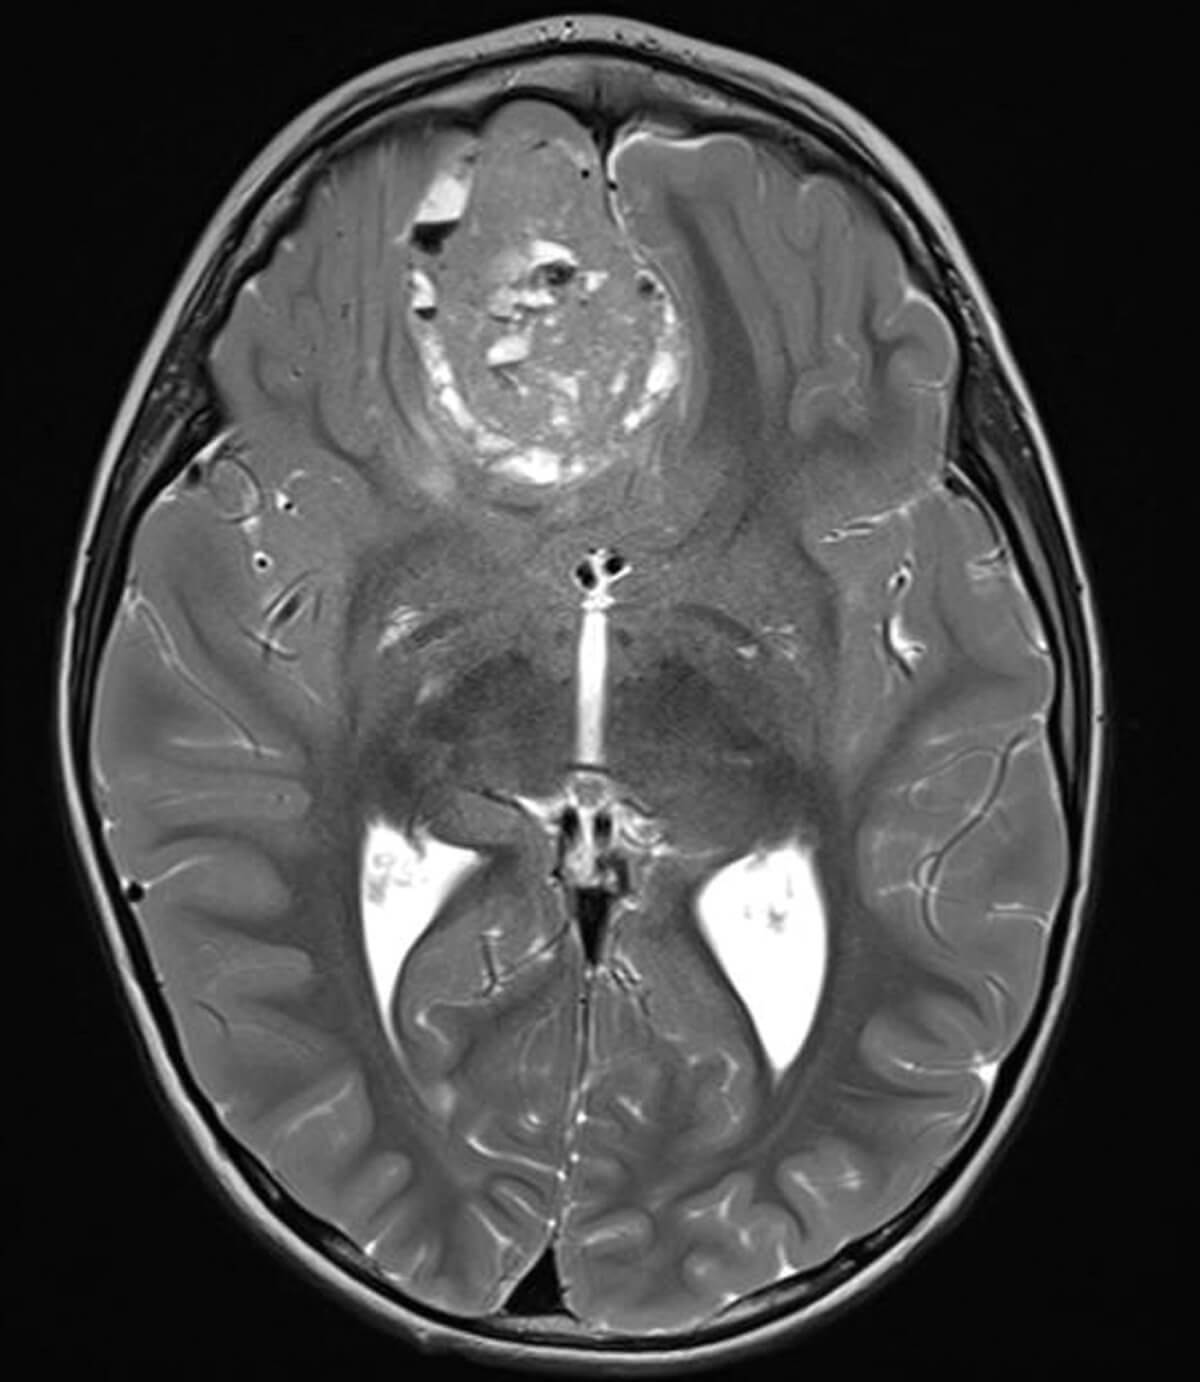

Figure 2: MRI showing large intracerebral mass.

Biopsy confirmed massive choroidal invasion, post-laminar optic nerve invasion, and surgical margins free of tumour - high-risk histopathological features which increased the risk of metastatic disease. However, no meningeal involvement was detected. Hereditary Rb was confirmed by genetic testing. Therefore, the child underwent four cycles of adjuvant chemotherapy. Despite this, the child presented with seizures three months later. Follow-up MRI revealed a large intracerebral mass (Figure 2) with meningeal infiltration. Lumbar puncture confirmed the presence of tumour cells in the cerebrospinal fluid, indicating CNS spread.